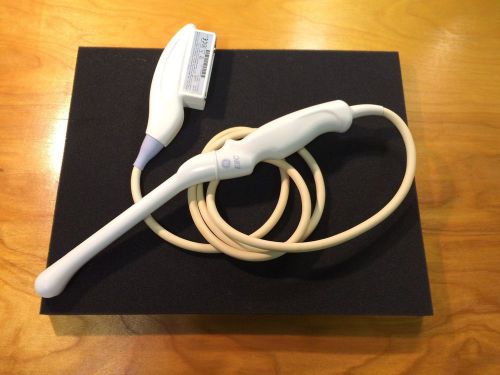

| “Enjoys good cosmetics, see images for functionality” |

| Brand | Siemens |

| Model | 08266709 |